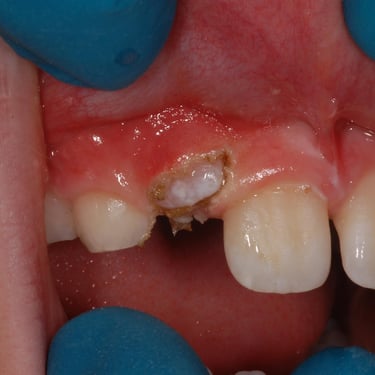

Dientes Supernumerarios

Los dientes supernumerarios son dientes adicionales que pueden aparecer en la boca y causar problemas de alineación o erupción de otros dientes.

Los pacientes pueden notar dientes adicionales en la boca, lo que puede causar apiñamiento o problemas estéticos.

El tratamiento incluye la extracción quirúrgica de los dientes supernumerarios.